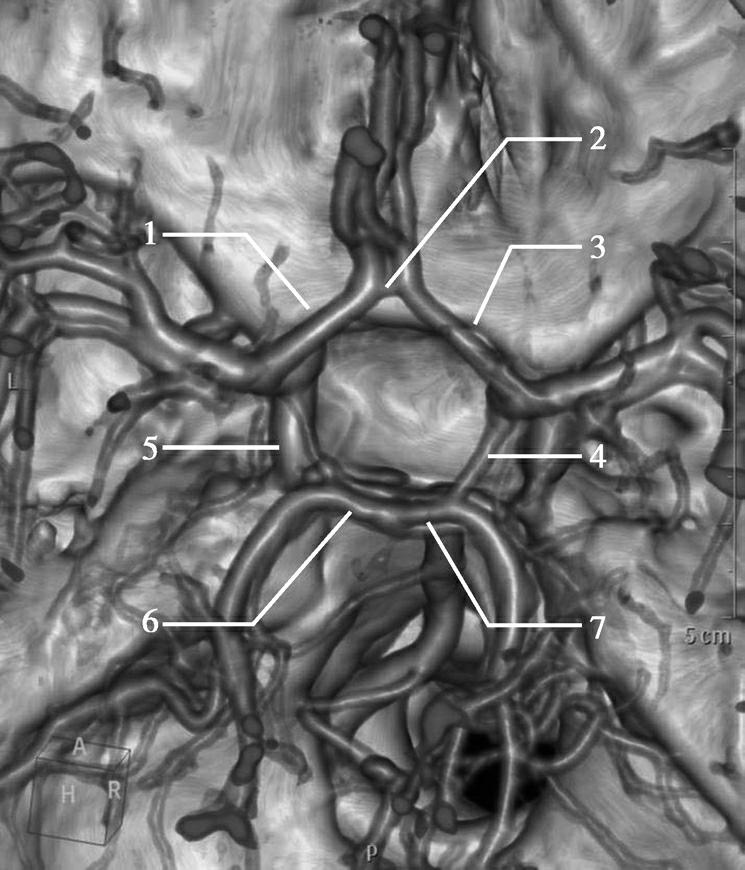

大脑动脉环又称Willis环,为连接大脑两半球前部循环及椎基底系统的大吻合环,呈多边形,由下列结构组成:两条大脑前动脉(ACA)交通前段(A 1 ),两侧大脑后动脉(PCA)交通段(P 1 ),两侧颈内动脉(ICA)末端,前交通动脉(ACoA),两侧后交通动脉(PCoA),两侧ICA在脑底通过ACoA相通,并且借PCoA与椎基底动脉系统相通(图1-2-86)。

图1-2-86 正常大脑动脉环

1.左侧大脑前动脉(ACA)交通前段(A 1 );2.前交通动脉(ACoA);3.右侧大脑前动脉(ACA)交通前段(A 1 );4.右侧后交通动脉(PCoA);5.左侧后交通动脉(PCoA);6.左侧大脑后动脉(PCA)交通段(P 1 );7.右侧大脑后动脉(PCA)交通段(P 1 )

大脑动脉环小而重要的穿支血管给许多重要结构供血,如垂体柄、垂体腺、丘脑、下丘脑视神经交叉、视神经、视束、基底节及中脑。对于闭锁性血管疾病,大脑动脉环是侧支血流最充分的供血来源,熟知其正常解剖、变异与异常十分必要。